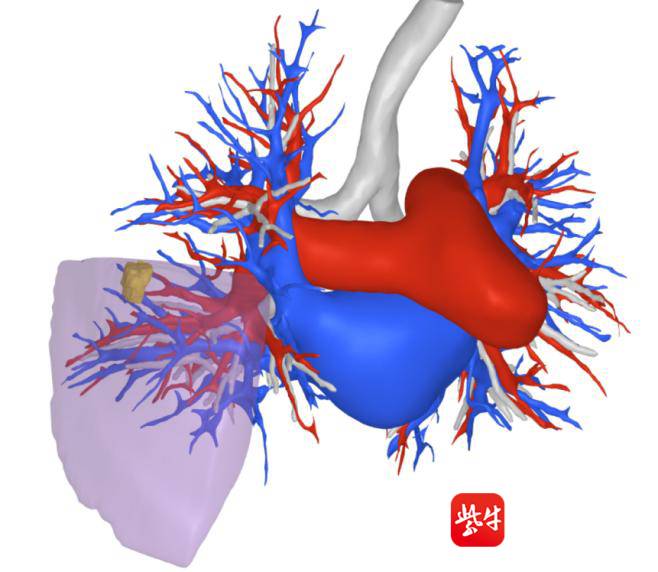

但在陈亮主任团队的细致评估与方案打磨下,患者张阿姨(化名)的手术从一开始就走上了“不一样的快车道”。术前,陈亮教授团队联合技术支持团队将张阿姨的CT影像导入专用系统,软件如同“智能绘图师”,瞬间自动生成一份肺部“全景导航图”——结节的大小、藏在肺部的具体位置,支气管蜿蜒的走向,肋骨与血管密密麻麻的分布,所有关键结构都清晰得像“标注好的地图”,相当于提前给手术团队画好了精准路线,彻底跟传统“凭经验盲穿”的不确定性说再见。

AI与AR技术的“强强联手”,还让张阿姨胸部器官的“数字孪生体”以3D形式实时呈现在潘医生眼前,这一画面同时通过电脑屏幕同步给团队其他成员,大家 “同看一张精准图”,最终,定位过程仅用了不到10分钟,效率大幅提升。随后,陈亮主任团队按照术前3D-CTBA规划的方案,顺利为张阿姨实施荧光胸腔镜右肺S4a单亚段切除术——不仅精准定位、“清除”了肺结节,更最大限度保留了正常肺组织,为她术后快速恢复、维持良好肺功能打下了坚实基础。

术前 3D-CTBA 规划

3D-CTBA指导下的胸腔镜肺亚段切除手术,是我院胸外科秉承“以患者为中心”理念的技术创新和成功实践。突破原有肺段切除术范畴,充分利用新技术,将切除手术推向解剖性呼吸单位,切除亚段、次亚段等更小范围,并实行多种形式的组合切除,让患者保留更多的健康肺组织,加之胸腔镜微创途径,堪称“微创中的微创”。